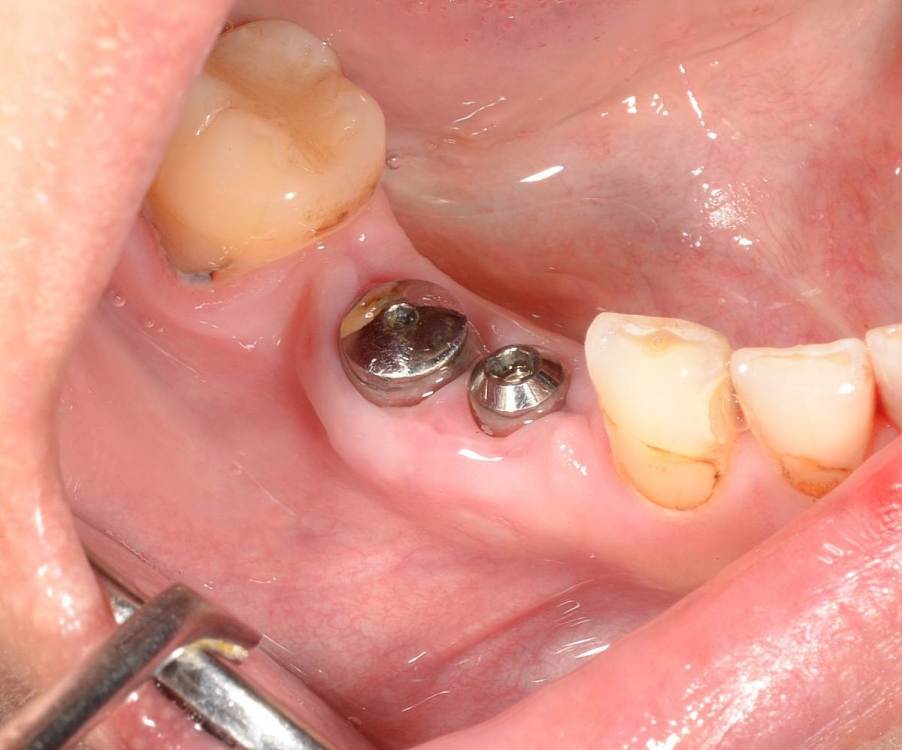

Большой Зеленый Опубликовано 27 мая, 2022 Поделиться Опубликовано 27 мая, 2022 Через 9 лет. Есть немного рецессии.. 2 Ссылка на комментарий

pit Опубликовано 27 мая, 2022 Поделиться Опубликовано 27 мая, 2022 4 часа назад, Большой Зеленый сказал: Через 9 лет. Есть немного рецессии.. Это связано исключительно с вестибулярной позицией импланта. Это как раз к вопросу про те минимальные 2мм до вестиболярной стенки, вне зависимости есть она или ты ее создаешь. Ссылка на комментарий

Большой Зеленый Опубликовано 27 мая, 2022 Поделиться Опубликовано 27 мая, 2022 4 часа назад, pit сказал: Это связано исключительно с вестибулярной позицией импланта. Это как раз к вопросу про те минимальные 2мм до вестиболярной стенки, вне зависимости есть она или ты ее создаешь. С тех пор я стал хитрее умнее и опытнее ))) 1 час назад, alboard сказал: А в чем смысл ее сохранности, если препарируя под имплантат вы все равно ее в большинстве случаев сносите? Первичная стабильность импланта зачастую достигается только перегородкой.. Ссылка на комментарий

Большой Зеленый Опубликовано 28 мая, 2022 Поделиться Опубликовано 28 мая, 2022 12 часов назад, Женька сказал: @Большой Зеленый это вроде ваш старый кейс? напомните пожалуйста, тут присыпка+мембранинг вестибулярно и вестибулярным лоскутом слегка послабленным всё закрыли? Да все так и есть как Вы и описали. Работе почти 10 лет. Присыпка мп3 от остеобила сверху "ильгамовская" губка . Считаю что результат вполне удовлетворительный. Рецессия обусловлена как уже сказали выше вестибулярным положением импланта ,ну и недозаглублен чуток. Ссылка на комментарий